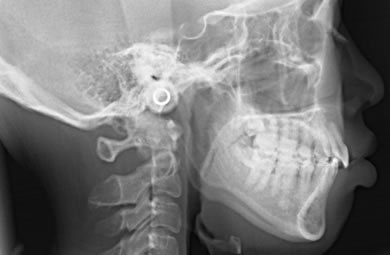

| 治療方針 | 口元が出ていていること、がたつきが大きいことより、上下左右の第一小臼歯および親知らずを抜歯し、マルチブラケット治療を行う。抜歯した隙間を活用できるよう上顎にはインプラントアンカー(釘)を使用し、その釘より歯を後ろに移動する。 | ||||||||||||||||||||||||||||||||

| 治療内容 | 唇側矯正(シルバー)、矯正用スピードインプラント、ハイブリッドセラミックインレー2本 | ||||||||||||||||||||||||||||||||